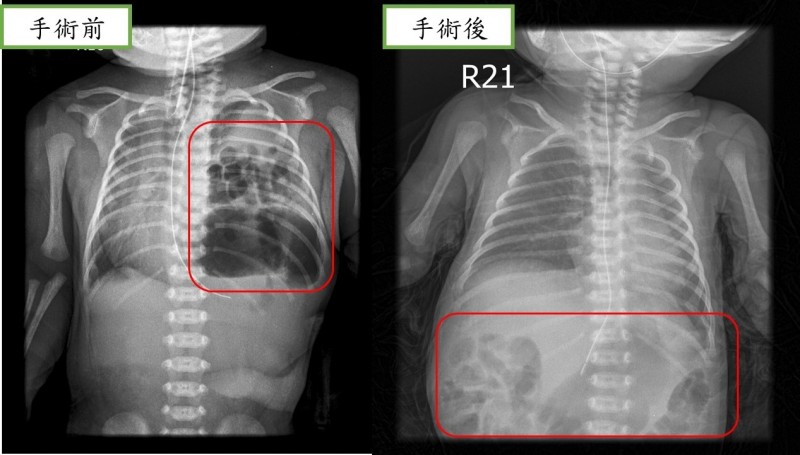

近日,重醫附屬兒童醫院心胸外科醫護團隊為這名男孩進行了手術,幫他將腸道送回腹腔,再補好了腹腔和胸腔中間膈肌的殘缺。手術順利完成。醫師提醒,孕產婦孕期一定按時要做好產檢,先天性膈疝最早可以在孕12周左右做產檢時通過彩超發現,如果孕期診斷,還應與其他畸形進行鑒別,同時根據多個指標評估胎兒膈疝病情的輕重,決定進一步處置方案。

孕期診斷後,要選擇合適的生產醫院,出生后及時轉運至有救治能力的專科醫院,依據病情嚴重程度和臨床表現決定手術時機,該疾病一旦診斷,原則上均需要儘早手術治療,減少對孩子的影響。